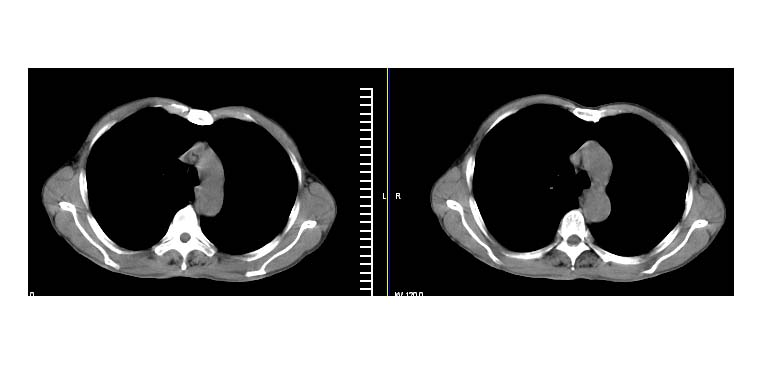

标题: CT11019:男性,66岁。发烧5-6天。治疗后无明显好转。 [打印本页]

标题: CT11019:男性,66岁。发烧5-6天。治疗后无明显好转。

左侧胸廓偏小,左下梭形高密度影,考虑阻塞性肺炎.

斜肋积液

右下肺中央型肺癌伴阻塞性肺炎及肺不张可能性大,建议临床进一步检查(ct增强或纤支镜)

斜裂积液,炎症

明明是斜裂胸膜积液,为何都考虑阻塞性肺炎、肺不张(边缘内凹,而本例是外凸)。